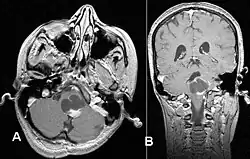

Kernspintomographie eines pilozytischen Astrozytoms der hinteren Schädelgrube mit zystischem Wachstum und Kontrastmittelaufnahme im Bereich des Hirnstamms.

Das pilozytische Astrozytom ist ein langsam wachsender astrozytärer Hirntumor, der vor allem bei Kindern und jungen Erwachsenen auftritt und den häufigsten gutartigen Tumor in dieser Altersgruppe darstellt. Als feingeweblich gutartiger Tumor wird er nach der WHO-Klassifikation der Tumoren des zentralen Nervensystems als Grad 1 eingeteilt und gehört zur Gruppe der sogenannten umschriebenen astrozytären Tumoren.

Pilozytische Astrozytome können im Bereich von Großhirn, Zwischenhirn, der hinteren Schädelgrube, des Rückenmarks und auch im Verlauf von Sehnerv (Nervus opticus) und Sehbahn (Tractus opticus) auftreten,[1] wobei in letzterer Lokalisation auch von Optikusgliomen gesprochen wird. Beidseitige Optikusgliome gelten als charakteristisch für die Neurofibromatose Typ 1.